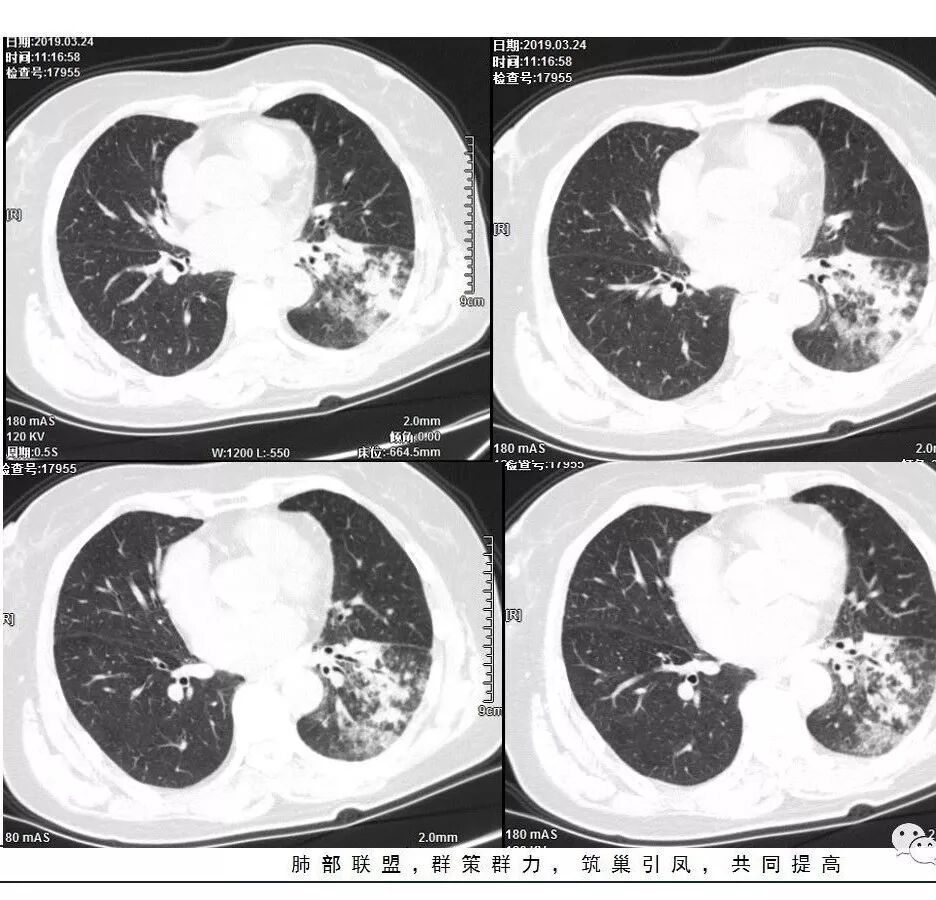

胸CT:左下叶基底段支气管狭窄,沿支气管分布斑片实变影、网格影、磨玻璃影,支气管充气征,无重力效应,左肺门淋巴结肿大、钙化。

左下叶实变影及磨玻璃影,内部支气管扩张、僵直。纵膈肺门淋巴结钙化。balf结核杆菌核酸阳性。

2、两肺马赛克灌注

3、两侧肺门区钙化淋巴结

两肺门钙化淋巴结一般考虑:结核?尘肺?淀粉样变性?

这是老问题:1、肺门区软组织密度影较弥漫;我们常规鉴别的就是结核?鳞癌?既往我们群里基本这两方向。2、弥漫的淋巴结钙化,加上马赛克灌注。马赛克灌注的原因是两个,一个是肺动脉的,一个就是小气道的问题。我们看增强的区域,没有看到栓塞,所以我倾向于小气道的问题,就是弥漫气道病变,慢性气道病变要考虑。我怀疑有没有淀粉样变性累及气道壁改变的可能。淀粉样变性是一个继发性病变,结核也可以,粉尘也可以。

这个病例支气管狭窄后扩张,肺门区有很多钙化的淋巴结,两肺弥漫的马赛克灌注,肺门淋巴结这么多,一个结核,一个尘肺,然后就是一个淀粉样变性,这几种最常见。鳞癌因为老年女性,除非吸烟,不太考虑,又不能绝对排除,所以就把鳞癌放到后。